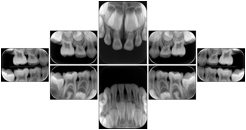

3. A dental provider wishes to capture a series of DICOM IO images for the patient’s dentition. The tooth morphology, teeth are divided into molars, premolars, canines and incisors, and a number of images for each jaw. The anatomic information was captured utilizing the triplet of schema. This standard code sequence is based on ISO 3950-2010, Dentistry - Designation system for teeth and areas of the oral cavity.

Every IO image should have anatomic information either through the primary or modifier sequence.

In most standard cases, images are oriented in structured layouts. These structured displays are useful to be shared between providers for reference purposes.

Table OO.1.1-1 shows structured display standard templates, where Viewset ID is based on the Japanese Society for Oral and Maxillofacial Radiology (JSOMR) classification provided by JIRA (Japan Medical Imaging and Radiological Systems Industries Association, www.jira-net.or.jp). Expected or typical teeth to be imaged location, region and designation codes are based on ISO 3950-2010, Dentistry - Designation system for teeth and areas of the oral cavity. For all the hanging protocols listed in OO.1.1-1, the value to use for Hanging Protocol Creator (0072,0008) is "JSOMR" and the value to use for Hanging Protocol Name (0072,0002) does not include "JSOMR" (e.g., "DL-S001A", not "JSOMR DL-S001A").